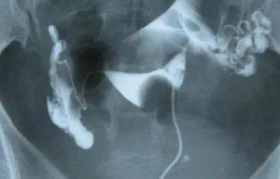

输卵管造影是一种常见的妇科检查方法,用于评估女性输卵管是否通畅及其形态是否正常。许多女性在进行这项检...